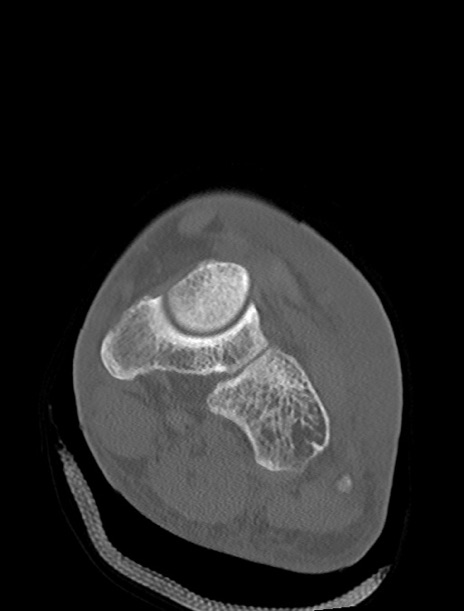

左足関節CT

横断像